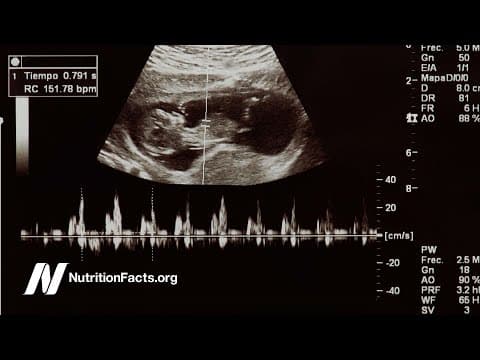

Prenatalna dijagnostika ovih anomalije je moguća ultrazvučnim pregledom u 2. i 3. tromjesečju trudnoće, a u zadnje vrijeme ta dijagnostika se pomiče u sve ranije periode trudnoće,te je neke od ovih grešake moguće otkriti ili posumnjati na njih i ranije, prilikom ultrazvučnog pregleda u kasnom 1. i ranom 2. tromjesečju.

Pored napretka tehnologije i sve razvijenijih ultrazvučnih aparata, srčane greške i dalje su na prvom mjestu neotkrivenih fetalnih anomalija, stoga je pored kvalitetne ultrazvučne opreme potrebno i znanje i stalna edukacija profesionalaca koji se bave fetalnom medicinom